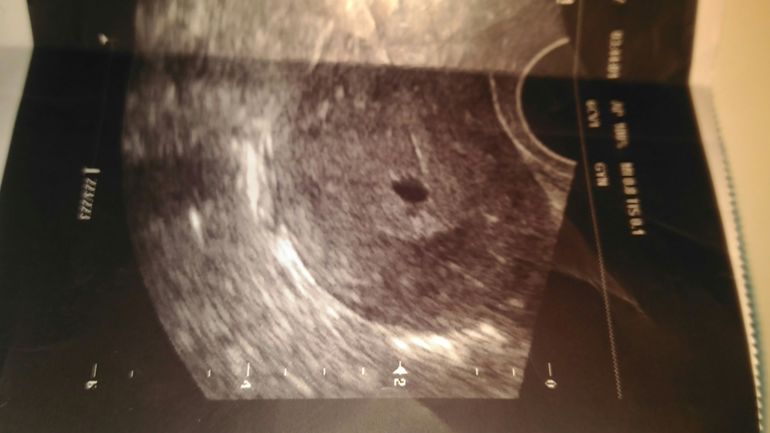

Девочки, подскажите у кого какие мысли, что это может быть? Была на узи, 16 день цикла при 35 дневном цикле, узистка говорит, что это желтое тело, вроде бы, но у меня были нормальные месячные 23 мая и тест отрицательный !!!

Татьяна, я тут всех запутала и сама запуталась это же не яичник, а матка, и врач аредполагает что это плодное яйцо, я неправильно написала от волнения

В матке желтого тела быть не может, оно в яичнике. Мне тоже кажется что это матка - тогда не понятно, что за пузырек в ней. А что в заключении?

Она писать не стала, сказала придти в пятницу,так как не понятно, хотя она сказала, что если это фолликул, все же, то тогда в левом яичнике, чего -то я сама совсем запуталась

Вот ла, девочки совсем запуталась, она предположила что это плодное яйцо, может это киста?сама сказала, с о странно, придите в пятницу